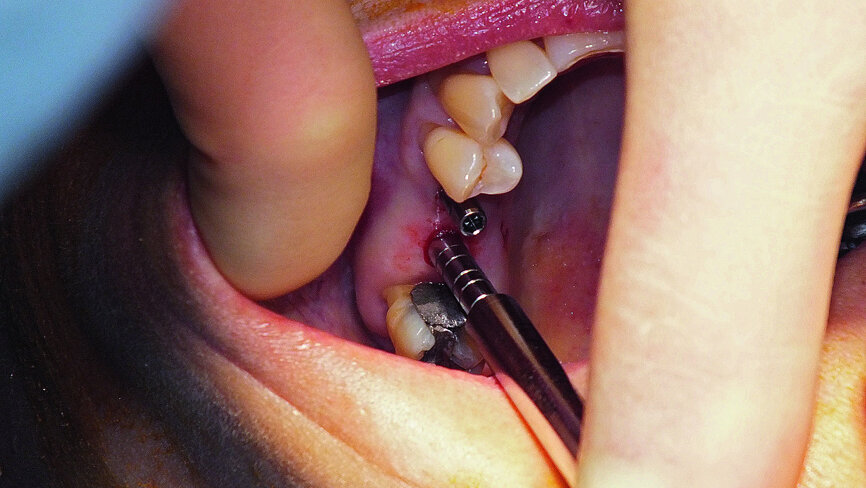

Fig. 6: Preparation of upper right second premolar implant site.

Treatment was carried out under local anaesthesia. The flapless procedure resulted in minimal trauma to the gingival tissue overlying the ridge. The previously constructed NaviStent, and the drill tag and jaw tag supplied by ClaroNav, were prepared immediately prior to surgery (Fig. 3). In accordance with the Navident protocol, the axis of the drill and tip of the pilot drill were calibrated (Figs. 4 and 5) and verified before site preparation commenced (Fig. 6). Using computer-guided surgery, the pathway of the drill could be followed clearly on the computer screen positioned in front of the patient (Fig. 7). Approximately 1 mm of bone was left intact in the upper right first molar site ready for the sinus lift. Navident provided visual confirmation of the position of the drill tip to accurately gauge the correct depth (Fig. 8). Preparation continued using a 3.5 mm drill bit, which, again, was calibrated and verified before use (Figs. 9 and 10).